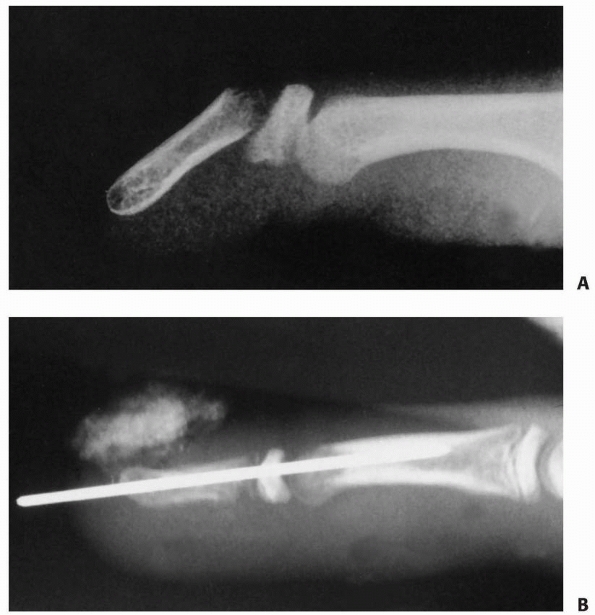

![]() |

FIGURE 8-8 A,B.

A 14-year-old girl with multiple enchondromas (Ollier disease), which weaken the bone and increase the susceptibility to fracture. (Courtesy of Shriners Hospitals for Children, Philadelphia, PA.) |